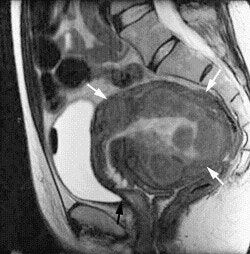

![]() |

| This sagittal FSE MR image, one-year post-UFE, shows a marked reduction in uterine volume and almost complete shrinkage of the submucosal fibroid, as well as a decrease in the size of intramural fibroids. Image courtesy of Dr. J. Mark Ryan. |